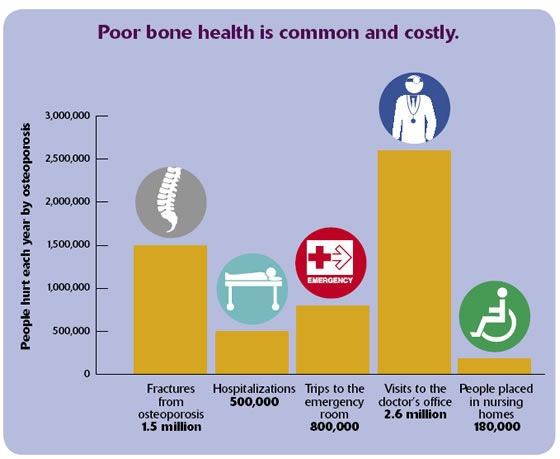

Osteoporosis and other bone diseases, such as Paget's disease and osteogenesis imperfecta, can lead to a downward spiral in physical health and quality of life including losing the ability to walk, stand, and dress. It can even lead to premature death. Weak bones can result in painful and debilitating fractures. Each year, 1.5 million Americans suffer a fracture because of weak bones. The most common breaks are of the wrist, spine and hip.

Hip fractures are by far the most devastating type of broken bone and account for almost 300,000 hospitalizations each year. Of hip-fracture patients: 20 percent die within a year of the fracture, and 20 percent end up in a nursing home within a year. Many become isolated, depressed or afraid to leave home because they fear falling.

Bone disease is costly for society and individuals with the disease. In the United States, care for bone fractures from osteoporosis costs nearly $18 billion each year. The cost from a hip fracture for one individual can be more than $81,000 during their lifetime.